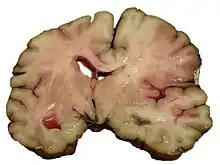

Intracerebral hemorrhage

It generally occurs in small arteries or arterioles and is commonly due to hypertension,[58] intracranial vascular malformations (including cavernous angiomas or arteriovenous malformations), cerebral amyloid angiopathy, or infarcts into which secondary hemorrhage has occurred.[2] Other potential causes are trauma, bleeding disorders, amyloid angiopathy, illicit drug use (e.g., amphetamines or cocaine). The hematoma enlarges until pressure from surrounding tissue limits its growth, or until it decompresses by emptying into the ventricular system, CSF or the pial surface. A third of intracerebral bleed is into the brain's ventricles. ICH has a mortality rate of 44 percent after 30 days, higher than ischemic stroke or subarachnoid hemorrhage (which technically may also be classified as a type of stroke[2]).